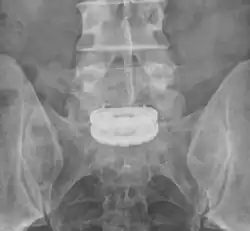

Die Abbildung zeigt einen Zustand nach Spondylodese der zwei untersten Lendenwirbelkörper (LWK4 und LWK5) mit dem ersten Sakralwirbel (SWK1) zwei Jahre nach der Operation. Der Zwischenwirbelraum zwischen dem vierten und dem fünften Lendenwirbelkörper ist bereits knöchern überbrückt (ankylosiert); beim Übergang vom fünften Lendenwirbelkörper zum ersten Sakralwirbel fehlt diese knöcherne Durchbauung. Wenn alle verblockten Wirbelkörper stabil knöchern miteinander verbunden sind, kann das Spondylodesematerial entfernt werden.

Dorsoventrale Spondylodese LWK5 – SWK1 -

Der gleiche Patient in der MPR -

Die Pfeile zeigen die knöcherne Durchbauung LWK4/5 und die fehlende Durchbauung LWK5/SWK1 an. -